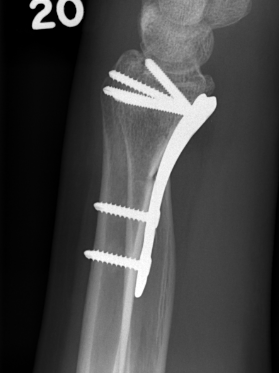

ORIF with locking plates

Advantages

Accurate restoration of intra-articular anatomy

Stable fixation with early mobilisation

Fragment specific plates

| Volar locking plates | Volar rim plates | Radial styloid plates |

Locking screws act as fixed angle devices Variable angle screws |

For very distal fracture fragments

Supplementary radial column fixation |

Volar locking plate technique

AO surgery modified Henry to distal forearm

Bed of FCR approach

- incision over FCR and mobilize ulnarly

- divide fascia in bed of FCR and retract radial artery laterally

- L shaped released of pronator quadratus

- cannot make volar capsulotomy - divides radiocarpal ligaments and causes instability

- elevate 1st extensor compartment (APL / EPB)

- release brachioradialis from radial styloid

Reduce fragments and temporarily stabilize with K wires

- apply volar plate with screw fixation in scaphoid and lunate fragments

- ensure not beyond watershed line to avoid flexor tendon irritation / rupture

- engage dorsal cortex but not too long to prevent EPL rupture

- on lateral, raise hand 30o to view joint

- +/- radial styloid plate if required